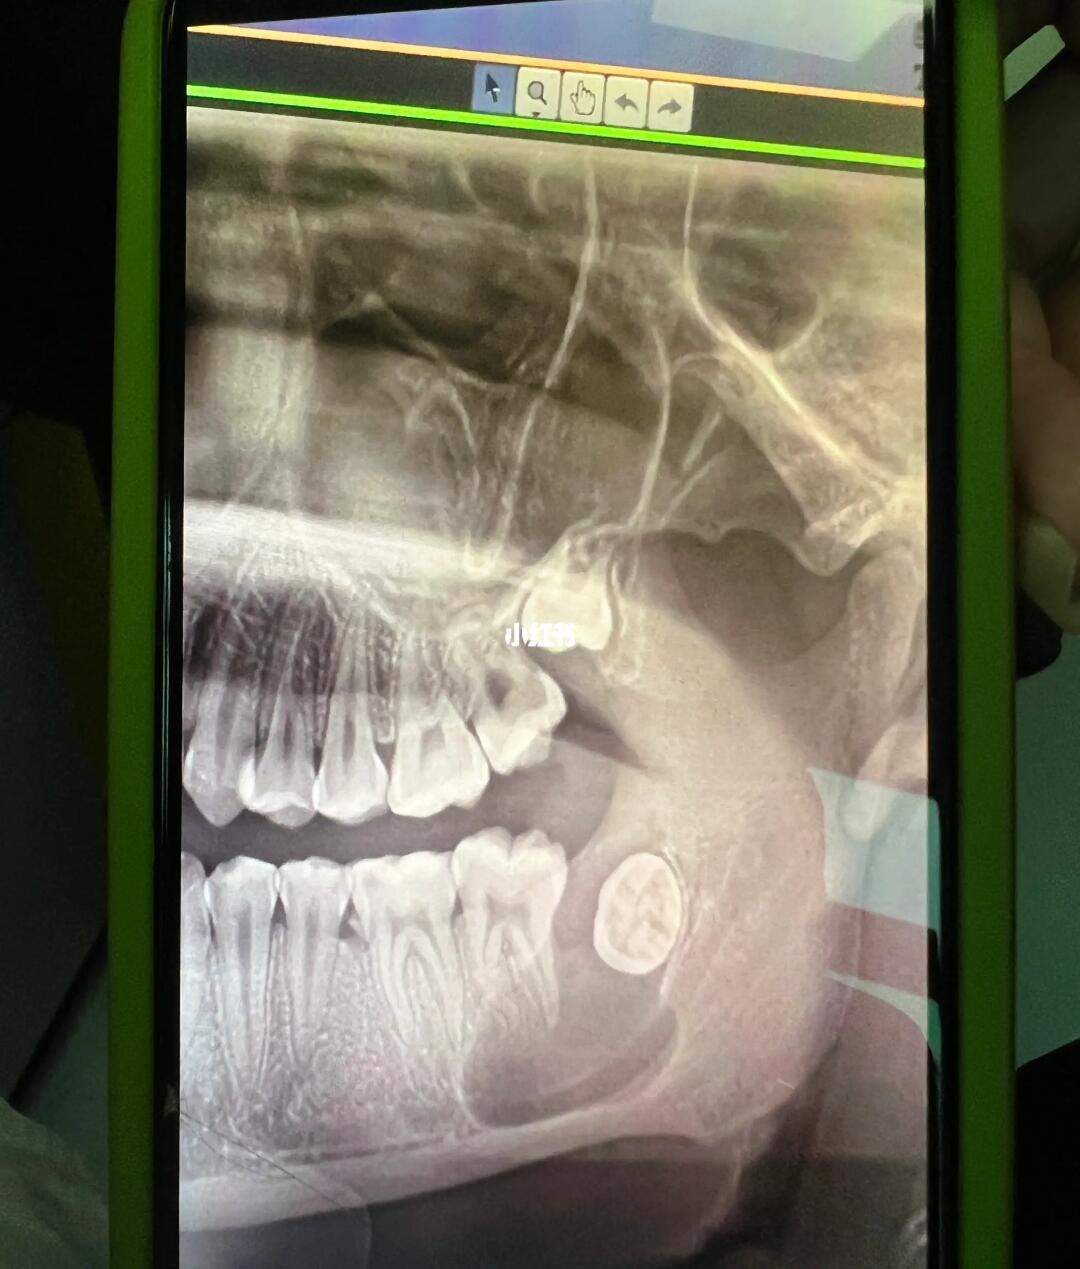

小伙颌骨囊肿手术后脸肿成🐷头!